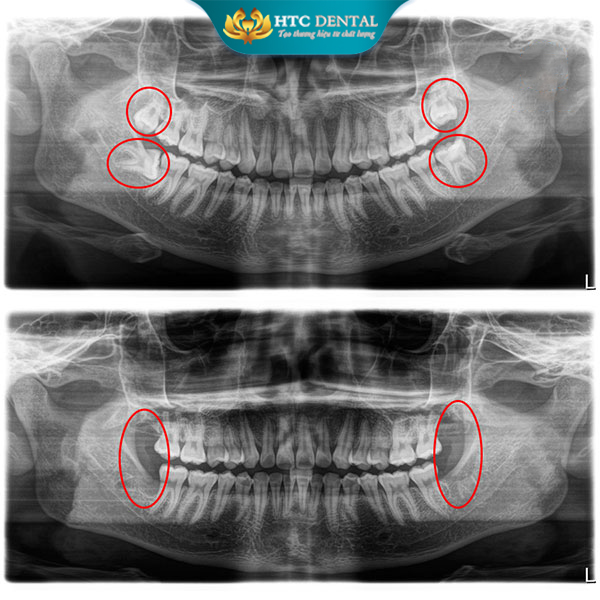

Cần chụp phim và tiểu phẫu

3.1. Chi phí chụp phim X-quang / CT

Hướng mọc răng

-

Độ sâu

Liên quan dây thần kinh

Hầu hết các ca nhổ răng khôn đều cần chụp phim trước khi nhổ.